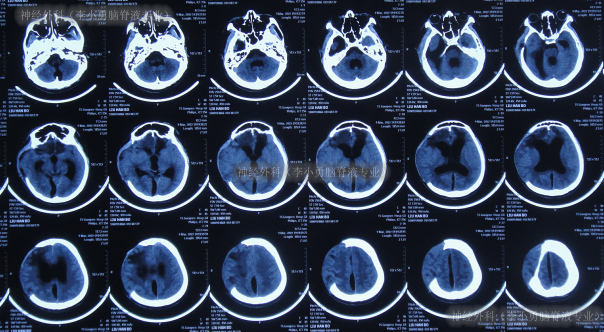

继续治疗1月期间出现数次呕吐,行胃肠镜检查未见异常(片子丢失),给予胃管及肠管置管,期间5次查头颅CT(图-5)均示脑室逐渐出现扩张,并加重。

图-5:5次查头颅CT

去骨瓣减压术后36天即2022年3月9日,复查头颅CT(图-6)示脑室扩张更严重了,脑膨出。

图-6:2022年3月9日头颅CT

去骨瓣减压术后43天即2022年3月16日,查头颅CT示仍严重脑积水(图-7)。

图-7:2022年3月16日头颅CT